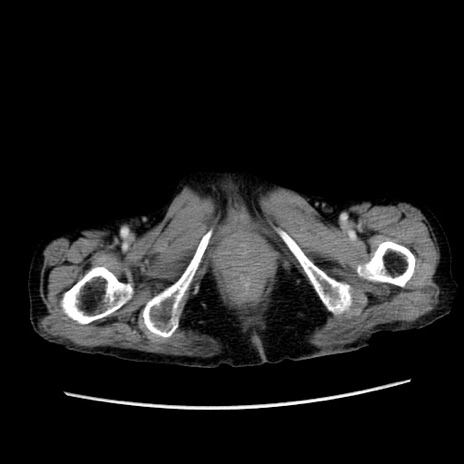

症例25(横断像)

【症例】80歳代女性

【主訴】胸のつかえ感

【現病歴】約9時間前に食後から胸のつかえた感じあり、嘔吐あり、来院。

【既往歴】胃癌(全摘)、胆摘、虫垂炎

【身体所見】心窩部に圧痛あり、反跳痛なし。

【データ】WBC 5700、CRP 0.05